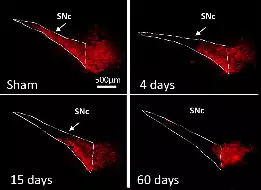

L’équipe étudie ces processus dans le contexte des fonctions et des pathologies liées aux ganglions de la base (BG), en particulier la MP, un trouble du mouvement caractérisé par la dégénérescence des neurones dopaminergiques du mésencéphale innervant le striatum, la principale station d’entrée des BG. Par le biais de collaborations, nos travaux abordent également des questions fondamentales et cliniquement pertinentes dans le contexte d’autres neuropathologies, notamment les troubles du spectre autistique (TSA), la maladie d’Alzheimer et la maladie de Charcot-Marie-Tooth.

L’étude menée par l’équipe de L. Kerkerian-Le Goff apporte les premières évidences en faveur d’un rôle de la protéine induite par le stress TP53INP1 dans le maintien de l’homéostasie neuronale en condition de stress lié au vieillissement normal et à la Maladie de Parkinson (MP).